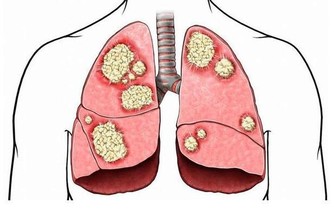

肝硬化發展到一定程度時易出現肝腹水,也就是腹中有太多積水,從而造成腹脹,導致放屁增多,以至於一天的排便次數大於10次。放屁次數跟肝硬化嚴重程度成正比,肝硬化病情越嚴重,放屁次數就越多。患有慢性肝炎、脂肪肝或酒精肝、長期服用藥物者,若放屁突然增多,還需及早去醫院做肝臟相關檢查,排除肝硬化的可能。